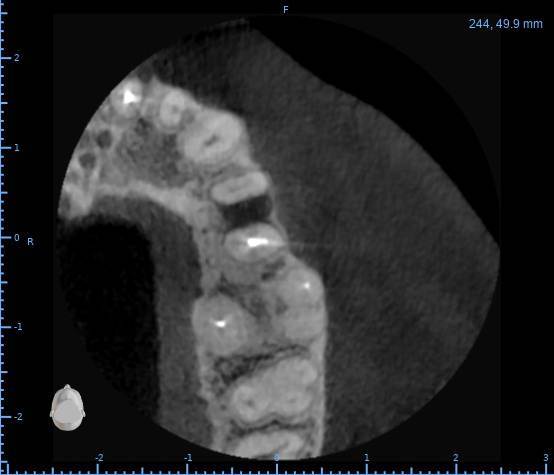

Здравствуйте, появился полгода назад свищ на десне, заполняется и лопается, затягивается и снова появляется, спустя пару месяцев обратился в стоматологию, на снимке ничего критичного не увидели, отправили домой наблюдать тип, еще прошло 3 месяца, так и не проходит и хуже не стало, болей нет никаких, только небольшая если трогать в районе свища, пойдя в другую стоматологию, сделали снимок и так же непонятно что и почему, пошел на КТ, и обратно в стоматологию, есть какая то полость, можно попробовать но нет гарантии, что пройдет, прикрепляю снимок К

ТРезультаты и плюс программа для открытия